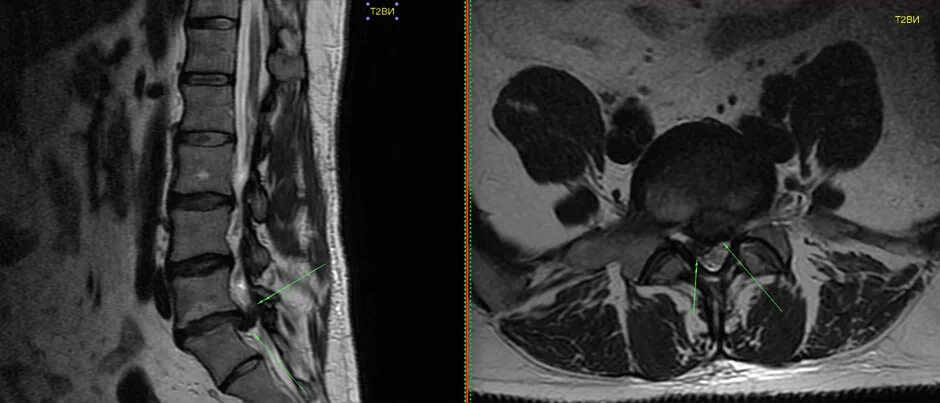

Как делают кт пояснично крестцового отдела